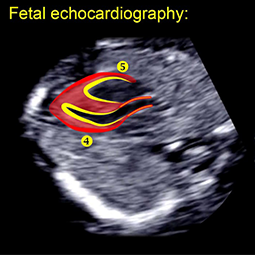

اکوکاردیوگرافی جنین چیست؟

اکوکاردیوگرافی جنین یک سونوگرافی جامع از قلب جنین است. مبدل یک دوربین کوچک است که امواج صوتی اولتراسونیک را منتشر می کند و روی شکم مادر باردار قرار می گیرد.

امواج اولتراسوند از قلب کودک منعکس می شود و به دوربین منتقل می شود، که تصویر متحرکی از بخش های مختلف قلب را برای تجزیه و تحلیل پزشک ارائه می دهد. جریان خون در سراسر قلب نوزاد را می توان با استفاده از امواج صوتی نیز تشخیص داد. این به پزشک اجازه می دهد تا آناتومی و عملکرد قلب نوزاد متولد نشده را ارزیابی کند.